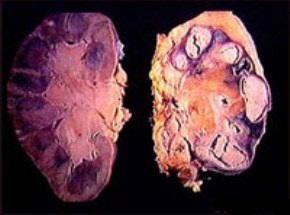

Дифференциальная диагностика при туберкулезе должна проводиться с гидронефрозом, уретрогидронефрозом, пиелонефритом (особенно с исходом в пионефроз и наличием гнойных свищей в поясничной области). Рентгенологические признаки туберкулезного процесса необходимо отличать от медуллярного некроза, осложняющего течение острого гнойного пиелонефрита, аномалий медуллярного вещества (губчатая почка, дивертикул чашечки, мегакаликс, мегакаликоз). Выключенные деструктивные очаги могут быть похожими на кистозные и плотные опухолевидные образования.

В случае деструктивного процесса решается вопрос об оперативном лечении (проводится предварительная 2-4 недельная противотуберкулезная терапия с последующей нефрэктомией). После нефрэктомии проводят противотуберкулезную терапию с целью предотвращения поражения единственной почки.

Если деструктивный процесс носит локальный характер, с поражением одного из сегментов почки, специфическая терапия должна сочетаться с дальнейшей резекцией пораженного очага (кавернэктомия) или санацией (кавернотомия).